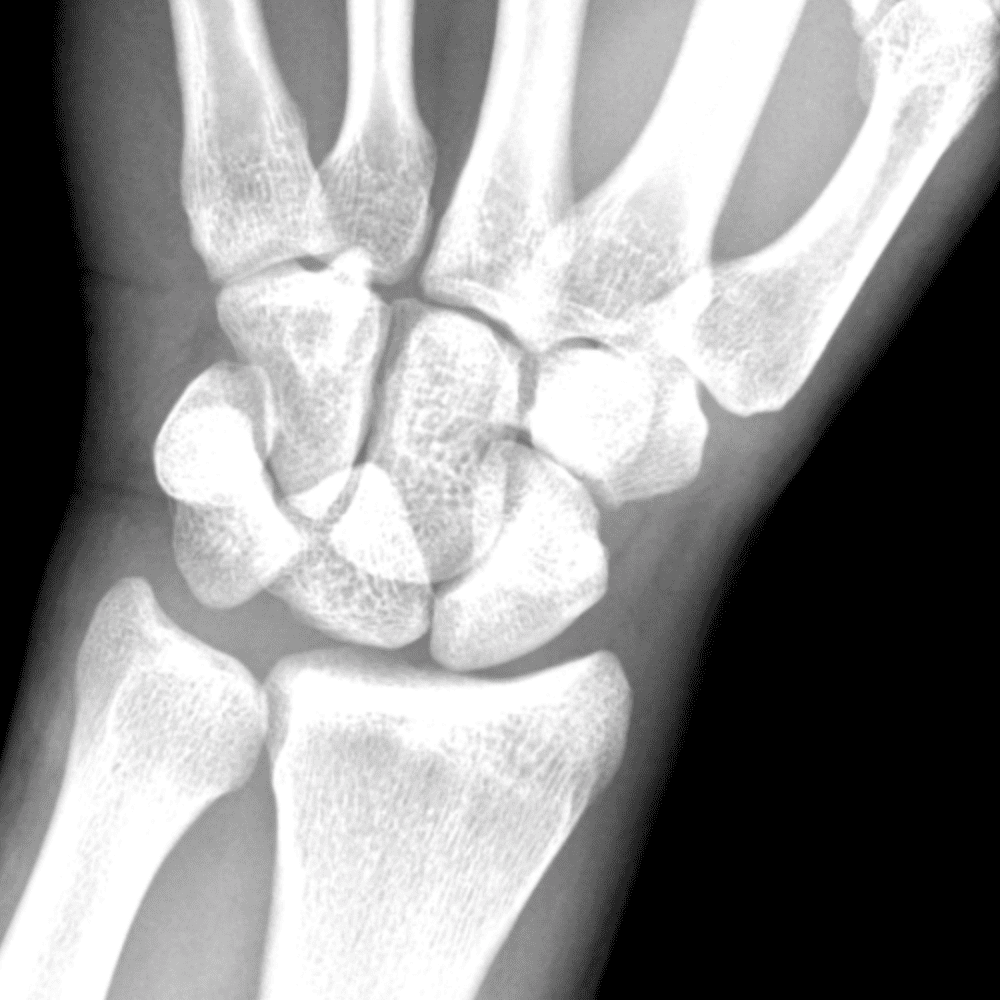

Simuliert den Dienst durch subtile oder schwierige Fälle und einige Normalbefunde.

30 Fälle